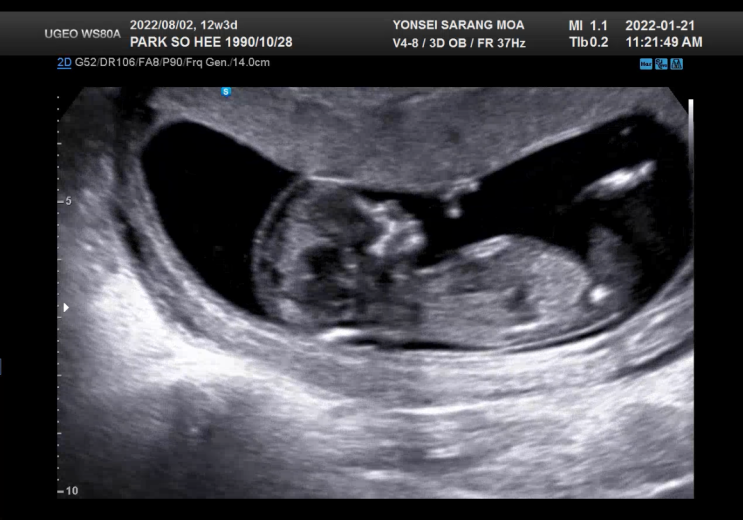

임신 9주 - 임신 13주_1차 기형아검사, 선물, 여전히 입덧

임신 9주, 10주, 11주. 특별한 일 없이 그냥그냥 지나갔다 입덧은 똑같았고, 늘 피곤했다 출퇴근은 자차로 ...